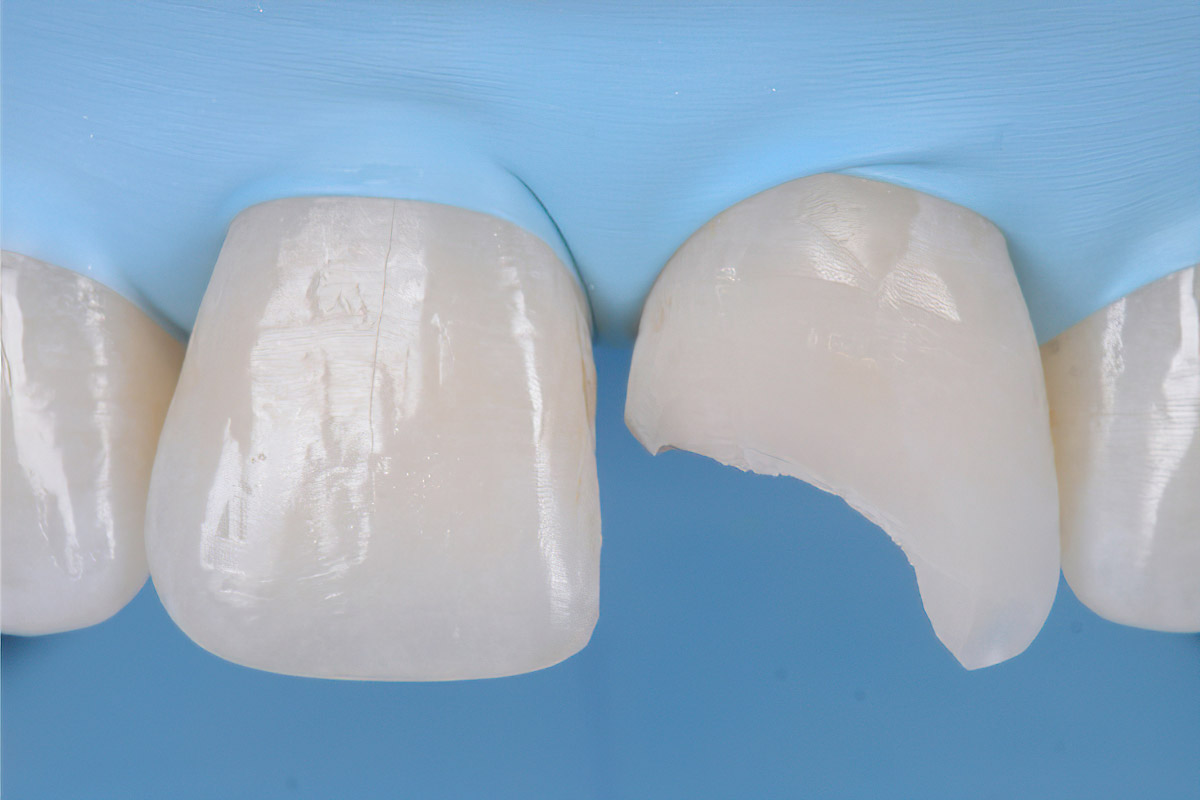

Anterior Case

Courtesy of Dr A. Mak, Australia